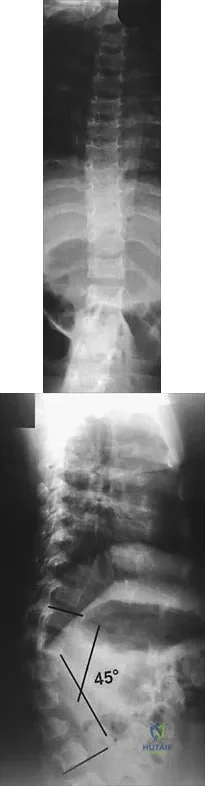

Question 45High Yield

Figures 9a and 9b show the spinal radiographs of a 3-year-old child with short limb dwarfism. The lateral radiograph is obtained with maximal lumbar extension. Management should consist of

Explanation